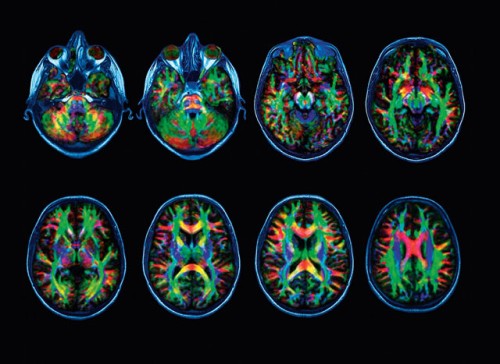

Kunstenaars hebben het vermogen om ver weg te blijven van die dikke verbindingen. Ze verlaten de hoofdweg en maken zijsprongen.

Voor een geboren kunstenaar is dat een tweede natuur. Anderen kunnen dat leren. Door zichzelf uit te dagen, obstakels in te bouwen of opdrachten te krijgen die sturen naar onvoorziene paden. Dat is het mooie werk dat we te doen hebben als we kunstenaarskwaliteiten bij onze leerlingen willen ontwikkelen.